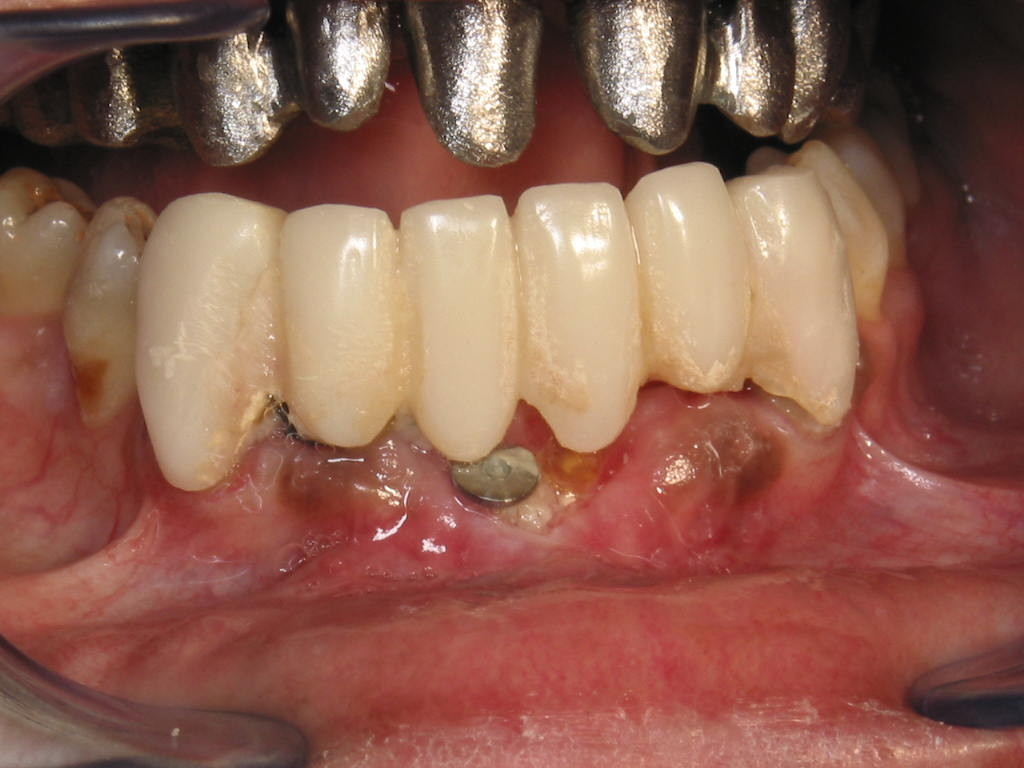

Injerto de mentón para conseguir aumento vertical y solucionar la recesión gingival. Fijación del injerto óseo con tornillo de osteosíntesis.

Provisionales, tratamientos endodónticos, ferulización con provisionales.

Prótesis definitíva en metal cerámica